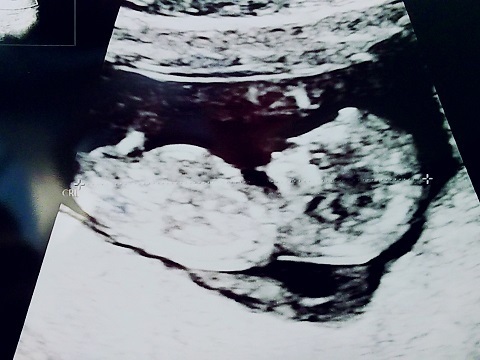

12週0日(12w0d・女の子)|yuki0255 さん(23歳)

エコー写真撮影時のエピソード:

初めの頃は、カシューナッツみたいで人間らしさもなかったのに、それでもそれがまたかわいくて次の検診が楽しみで毎日を過ごしていて、やっと人間らしくなって前よりも愛おしく思えました。

今でも寝る時は横を向いて寝るので、お腹の中と同じポーズだなぁと思いながら我が子を眺めてます。